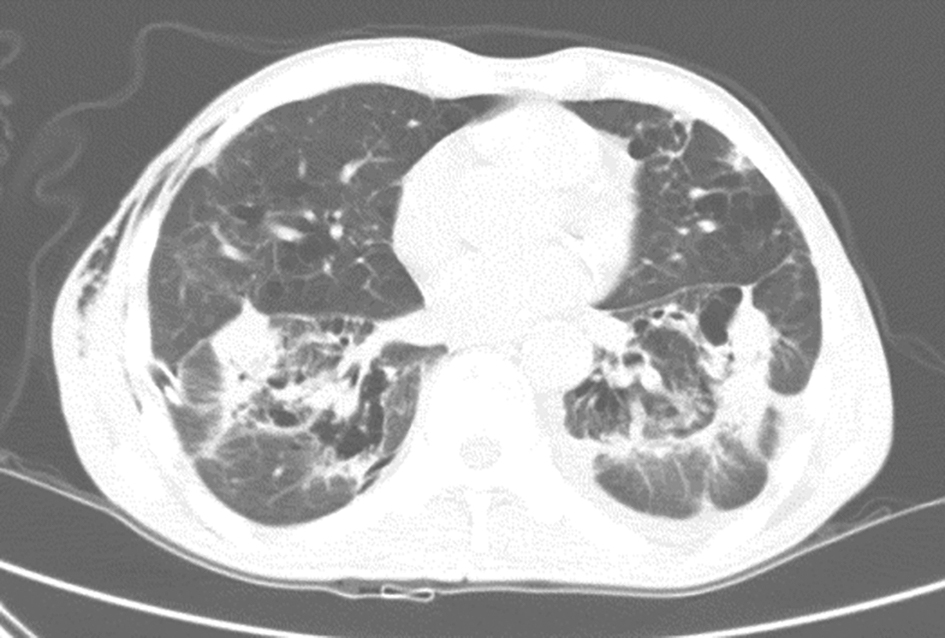

结合患者住院期间发现有糖尿病,发病前未接受任何治疗,入院后查HbAlc明显升高证实其血糖控制欠佳;影像学检查显示病变主要位于双上肺尖后段,呈团片状实变影,纵隔窗上可见较多坏死低密度区,双肺多发结节,结节边缘不规则,结节周围有卫星灶及树芽征改变,故需警惕肺结核可能,可进一步查抗结核抗体、PPD试验及多次送检痰涂片抗酸染色,同时可进行经支气管肺活检或经皮肺穿刺活检。其次,患者虽否认有鸽粪及鸟禽类等接触史,但仍需注意排除肺隐球菌病,可查气管镜活检协助诊断。

对于非感染性疾病,本例患者双上肺病灶范围大,边缘不规则,有分叶及锯齿征、空泡改变,同时双肺弥漫多发结节,需要考虑肺恶性肿瘤可能。患者无其他系统损害,肺内病灶空洞不明显,因此不考虑韦格纳肉芽肿等非肿瘤性疾病。